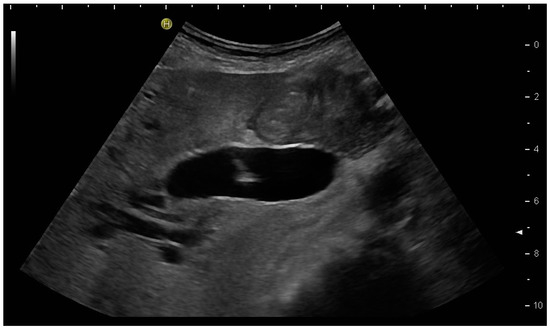

Most authors recommend a transhepatic approach in order to prevent biliary leakage to the abdominal cavity during drainage or after removal of drainage [43,55,56,76,77] (Figure 9).

(a) Transhepatic puncture of an inflamed gall bladder in the in-plane technique. The Chiba needle is depicted well; (b) A few days later, laparoscopic cholecystectomy was performed. The drainage ran through Segment V of the liver. It was removed without provoking biliary leakage from the liver parenchyma.

The consideration is that a perforation in the hepatic surface of the gallbladder will be covered by the liver tissue after the removal of the drain. However, retrospective analyses comparing the transhepatic route with the transperitoneal (i.e., nontranshepatic) access (Figure 10) report no differences in the complication rates [58,78,79].

PGBD without passing the liver and using the trocar technique: straightened drainage passes right below the lower liver margin into the gallbladder.

Again, the “in plane” approach is recommended to depict the needle in real time and continuously on its way. This is mandatory because iatrogenic perforation of the posterior gallbladder wall must be avoided. Both the drainage techniques, Seldinger (Figure 11a–c) and trocar (direct puncture, cf. Figure 10), may be used, depending on the physician’s preferences [43,58].